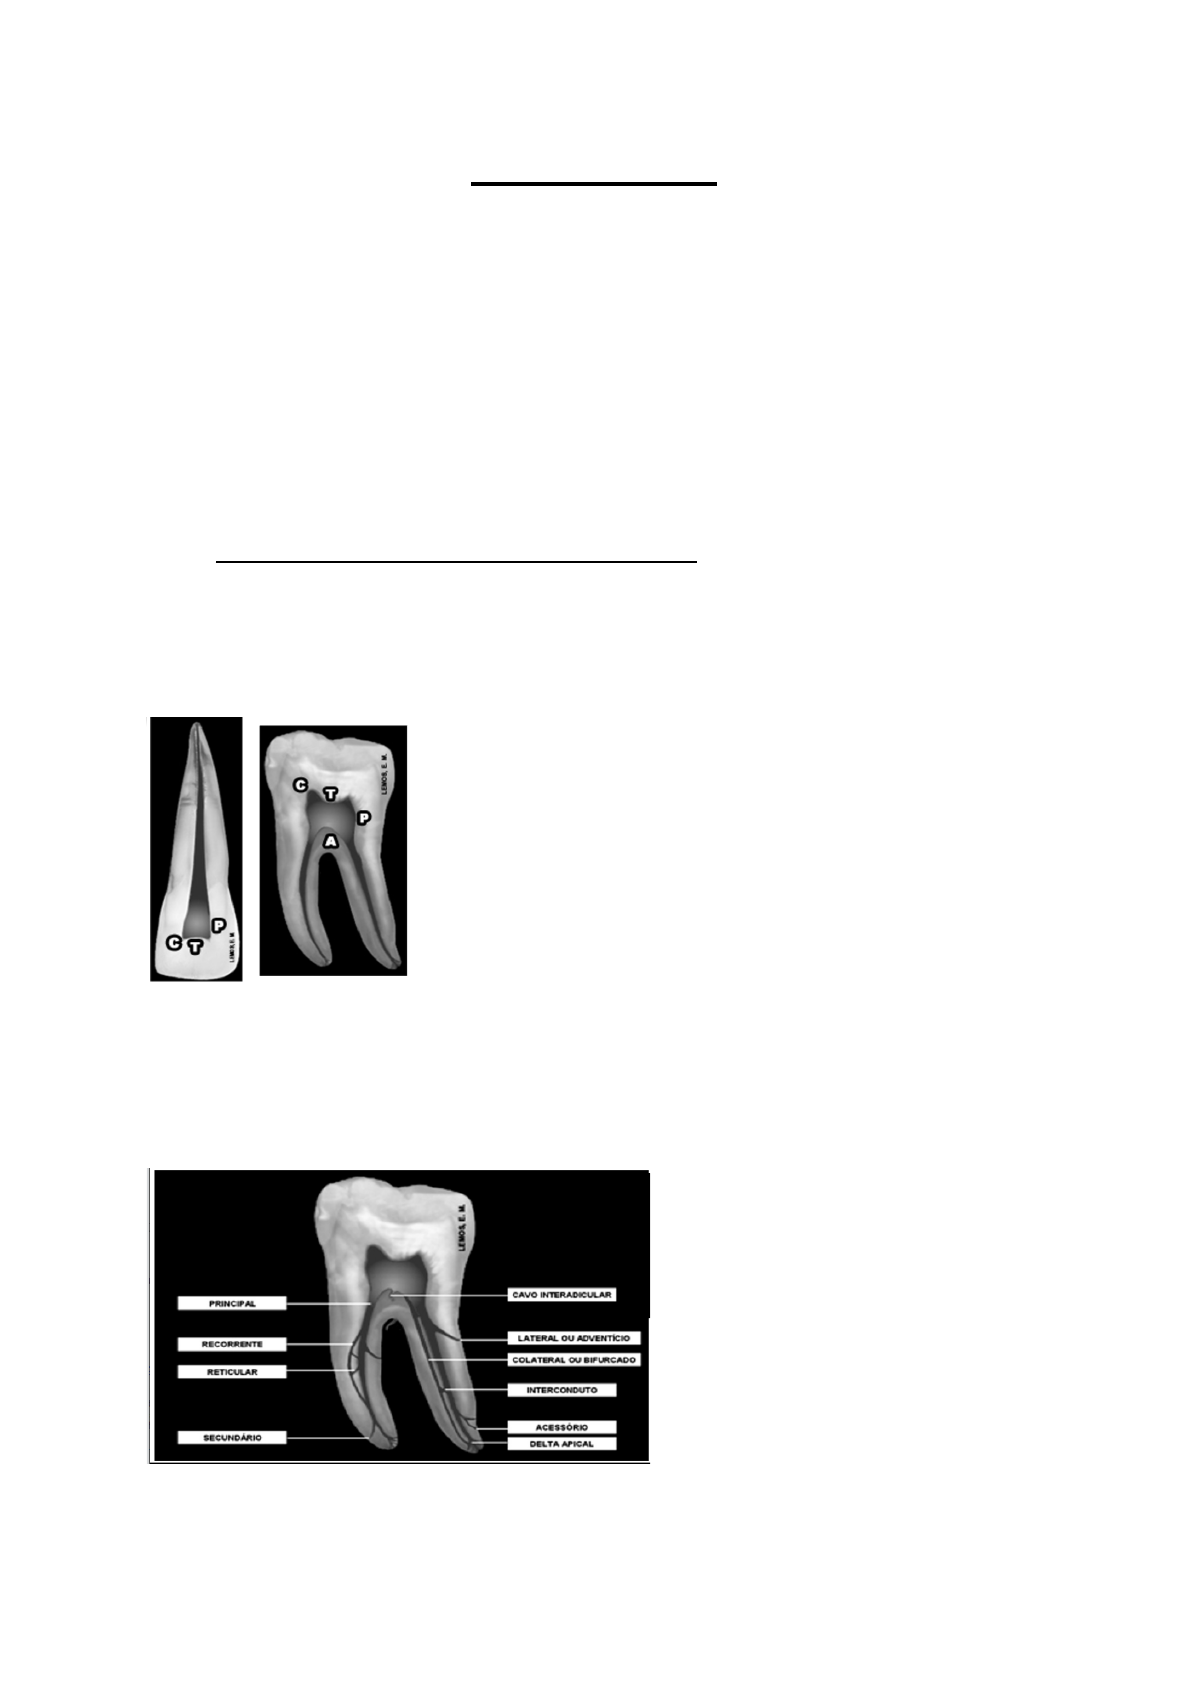

<p>Endodontia</p><p>Para uma endo de sucesso é necessário ter :</p><p>● Uma boa análise radiográfica : Observar o volume da câmara pulpar e presença de</p><p>cárie,presença de curvaturas acentuadas, presença de nódulos pulpares e</p><p>calcificações</p><p>● Uma boa exploração do canal</p><p>● Um bom conhecimento anatômico interno geral e individual dos dentes</p><p>1. Anatomia interna geral dos dentes :</p><p>→ Cavidade Pulpar :</p><p>- Espaço onde a polpa do dente está presente</p><p>- Se divide em câmara pulpar e canal radicular</p><p>- A câmara pulpar é composta por faces</p><p>A : Assoalho</p><p>C: Cornos pulpares ( extremidade da câmara pulpar)</p><p>P : Paredes</p><p>T : Teto da câmara pulpar</p><p>- O canal principal radicular se ramifica em variados :</p><p>Na ponta do assoalho ( região cervical</p><p>do canal) da câmara pulpar há o cavo inter radicular; no ápice do canal há o canal delta</p><p>apical.</p><p>- O canal radicular é dividido em terços : Cervical, médio e apical</p><p>Na sua porção há apical, o canal delta apical forma um forame principal e foraminas; há</p><p>presença de um canal cementário e dentinário ( canal principal) e há uma diminuição do</p><p>diâmetro do canal nas proximidades do canal dentinário e canal cementário ( CDC)--></p><p>chamado de cone invertido → ele tem em torno de 0,5 a 1 mm de distância.</p><p>Obs : A câmara pulpar pode ter alterações volumétricas podendo ser fisiológicas, como</p><p>idade avançada ou não fisiológica, como processo carioso</p><p>1.1 Anatomia dos dente anteriores e pré-molares :</p><p>a) Incisivo central superior: Possui apenas 1 canal, com uma raiz cônica piramidal de</p><p>forma mais retilínea→ Ao “cortar” a raiz no “meio” conseguimos ver que sua secção</p><p>é circular, com comprimento médio de 23mm</p><p>b) Incisivo lateral superior : Possui apenas 1 canal, com uma raiz trapeizodal com um</p><p>achatamento mésio-distal e inclinação no sentido disto palatino→ Ao “cortar” a raiz</p><p>no “meio” conseguimos ver que sua secção é circular , com comprimento médio de</p><p>22 mm</p><p>c) Incisivo inferiores : Possui apenas 1 canal, com uma raiz trapezoidal de pequeno</p><p>volume e um achatamento mésio-distal acentuado formando nas suas faces</p><p>proximais,mormente na distal, sulcos, normalmente possui forame único → Ao</p><p>“cortar” a raiz no “meio” conseguimos ver que sua secção é elipsóide , com</p><p>comprimento médio de 21 mm.</p><p>d) Canino superior : Possui apenas um canal, com uma raiz cônica piramidal de grande</p><p>volume mais retilínea, apresentando uma curvatura disto-vestibular —> Ao “cortar” a</p><p>raiz no “meio” conseguimos ver que sua secção é circular, com comprimento médio</p><p>de 27 mm</p><p>e) Canino inferior : Possui apenas um canal com uma raiz cônica piramidal mais</p><p>achatada mesio distalmente que o superior, normalmente apresenta forame único,</p><p>Ao “cortar” a raiz no “meio” conseguimos ver que sua secção é ovóide, com</p><p>comprimento médio de 25 mm</p><p>f) Primeiro pré molar superior: Apresenta dois canais, com duas raízes com maior</p><p>achatamento na raiz vestibular —> Ao “cortar” a raiz no “meio” conseguimos ver que</p><p>sua secção na porção cervical e medial mais circular e na porção apical mais ovóide,</p><p>com comprimento médio de 21 mm. Obs : pode ter variedades na divisão e fusão</p><p>g) Segundo pré molar superior : Apresenta apenas um canal, com uma raiz com</p><p>achatamento bem acentuado → Ao “cortar” a raiz no “meio” conseguimos ver que</p><p>sua secção é elíptica, com comprimento médio de 22 cm. obs : Pode haver</p><p>duplicidade de cana em raiz bifurcada ou em raiz única</p><p>h) Primeiro pré molar inferior : Apresenta um canal, com uma raiz achatada mesio</p><p>distalmente e com uma curvatura disto-lingual, com maior diametro V-L→ Ao “cortar”</p><p>a raiz no “meio” conseguimos ver que sua secção na região cervical e media é</p><p>ovalada e na apical circular, com comprimento médio de 22 cm. Obs : Pode</p><p>apresentar dois ou três canais com divisão ao nível médio ou apical</p><p>i) Segundo pré molar inferior :Anatomicamente parecido com o 1 PMI, apenas muda</p><p>que possui menos frequência de possuir dois canais.</p><p>OBS : Variações anatômicas : o incisivo inferior pode apresentar dois canais ; o canino</p><p>inferior pode apresentar uma bifurcação radicular; dens in dente → invaginação da camada</p><p>intermediária da papila dental, os dentes que ocorre com mais frequência são os ILS; Fusão</p><p>—> junção de duas coroas com uma única raiz</p><p>2. Instrumentos endodônticos:</p><p>2.1 - Instrumental Clínico :</p><p>- Escavador de dente: Retira a dentina amolecida</p><p>- Sonda exploradora reta e número 5 : Analisar se há ainda teto</p><p>- Sonda milimetrada : Avaliar o periodonto</p><p>2.2 - Diagnóstico :</p><p>- Espelho : Dar umas batidas no dente para ver se o paciente sente dor</p><p>- Endo- frost : Analisar se há polpa ainda está viva ou morta por meio de uma</p><p>temperatura de -50 graus ( teste para o frio)</p><p>- Guta percha : teste para o quente</p><p>- Radiografia</p><p>2.3 - Anestesia : Carpule e anestésico</p><p>2.4 - Cirurgia de acesso : Necessário o uso de instrumentos rotatórios ( caneta de</p><p>alta )</p><p>- Uso de broca esférica carbide de número 2 e 4 ; ou Pontas diamantadas de</p><p>número 1011-1016, dependendo do dente que vai ser acessado → Começar</p><p>acessar o dente.</p><p>- Uso de brocas tronco cônicas/endo-z, long neck ou transmetal→ para</p><p>remover o teto —> entrar com ela a 45 graus</p><p>2.5 - Isolamento : Grampos ( 00,2,2A,3,7,8,8A,9,14), lençol de borracha , porta</p><p>grampo, pinça e arco de ostby</p><p>2.6- Preparo da embocadura</p><p>- Broca largo :Possui uma forma cilíndrica, possui uma ponta inativa, sua ação</p><p>é por meio de penetração e retrocesso, ela prepara o terço cervical</p><p>- Brocas gates-glidden : Possui formato de pera, possui uma ponta inativa ,</p><p>sua ação é por meio de penetração e retrocesso , remove o material</p><p>obturador e prepara o terço cervical e médio → usa- se mais a gattes por ter</p><p>menor diâmetro, consequentemente mais facilidade em fazer o preparo. É</p><p>necessário ter cuidados com fraturas e não realizar movimentos pendulares</p><p>2.7- Odontometria</p><p>- Régua flexível ( comprimento do dente) e régua calibradora ( Comprimento</p><p>da lima )</p><p>- Localizador apical</p><p>2.8- Irrigação e aspiração : esses instrumentos servem para manter os detritos em</p><p>suspensão e para haver os movimentos dos fluídos devido a diferença de pressão</p><p>dentro e fora do canal.</p><p>- Agulhas (5 mm) e seringas ( 3 a 5 ml) hipodérmicas</p><p>2.9- Lima endodôntica : Instrumental metálico cortante que possui a função de</p><p>retirar os microorganismos</p><p>- As primeiras limas criadas possuíam sua parte ativa com farpas, formava</p><p>canais amplos e retos, facilidade em fraturar. Ela funcionava por meio da sua</p><p>introdução no canal, fazia de 1 a 2 rotações e tirava</p><p>- Após um tempo foram criadas as limas do tipo K → úteis na remoção de</p><p>dentina</p><p>Até que criaram a padronização dos instrumentos para facilitar o tratamento de</p><p>canal ao redor do mundo.</p><p>- Padronização dos instrumentos</p><p>As limas passaram a ter um</p><p>comprimento, um diâmetro para facilitar na hora da instrumentação. Ela é divida em</p><p>cabo ( onde está presente o número que representa o grau de espessura do guia de</p><p>penetração da lima, que está em cm, para passar pra mm é só dividir por 100, e o</p><p>formato de lima), parte intermediária (tamanho diverso) e parte ativa ( possui um</p><p>tamanho fixo de 16mm)</p><p>- Elas são numeradas de 1 a 140 ( o número que está no cabo significa a</p><p>espessura do guia de penetração daquela lima ) e possuem 3 séries que</p><p>avançam de 5 em 5 até a de 60 depois vão de 10 em 10 até chegar no 140</p><p>→ A 1 série vai de 15 a 40; A 2 série vai de 45 a 80 e a 3 série vai de 90 a</p><p>140.</p><p>Obs : Existe uma série especial de número 6 ( rosa) , 8 ( cinza) e 10 (lilás) → são</p><p>limas mais finas que as limas das séries, usadas em canais atrésicos, com</p><p>calcificação.</p><p>- As limas possuem três comprimentos de 21, 25 e 31; sendo que sua parte</p><p>ativa sempre terá 16mm, então o que muda é o comprimento da sua porção</p><p>intermediária.</p><p>- Ao fazer a instrumentação é necessário que o canal fique em forma cônica</p><p>( maior na região cervical e menor na região de ápice), então é necessário</p><p>fazer a conicidade do canal</p><p>É importante saber que a cada milímetro da ponta ativa ele SEMPRE aumenta 0,02</p><p>milímetros, então ao chegar no final da ponta ativa , ele possui um diâmetro maior</p><p>do que o da guia de penetração ( D0)--> Ex : Uma lima de comprimento 21 e</p><p>diâmetro</p><p>da guia de penetração 15, possui o seu D0 igual 0,15 mm , então qual é o</p><p>calibre do D6 dessa ponta ativa?</p><p>D6 : D0 + 0,02 x D6 = D6 : 0,15 + 0,02 X 6= 0,27</p><p>- Tipos de lima :</p><p>1) Lima do tipo K</p><p>- Sua secção é quadrada</p><p>- Tem torção inox</p><p>- Disponível em todas as série e nas séries especiais</p><p>- Auxilia na limpeza do canal ( limagem - movimento de introdução do</p><p>instrumento no canal, pressionando-o contra a parede do conduto por meio</p><p>dos movimentos giratórios ¼ horários e anti-horários e retirando-o,</p><p>removendo a dentina contaminada) —> mais usada em canais retilíneos</p><p>- Tem maior resistência pois seu ângulo de corte é de 90 graus, porém é a que</p><p>possui menor pode de corte</p><p>2) Lima do tipo flexo file</p><p>- Sua secção é triangular</p><p>- Tem torção em inox</p><p>- Está disponível só em primeira série</p><p>- Auxilia no alargamento do canal e na limpeza do canal ( limagem -</p><p>movimento de introdução do instrumento no canal, pressionando-o contra a</p><p>parede do conduto por meio dos movimentos giratórios ⅓ horários e</p><p>anti-horários e retirando-o, removendo a dentina contaminada)</p><p>- Tem menor resistência que a tipo K pois possui menor ângulo de corte (60</p><p>graus), porém tem um mais poder de corte que a tipo K e possui maior</p><p>flexibilidade, bom para canais com curvatura</p><p>3) Lima do tipo Hedstroem</p><p>- Sua secção é em formato de vírgula</p><p>- Está disponível em primeira,segunda e terceira série</p><p>- Faz a limagem do canal mas sem giros</p><p>- Possui alto poder de corte por possui um menor ângulo de corte (42),</p><p>consequentemente menos resistência</p><p>- Muito eficaz na remoção de dentina e ampliação do canal</p><p>4) lima do tipo C+</p><p>- Mais resistente → bom para canais calcificados</p><p>- Tem uma ponta em forma de pirâmide</p><p>- Secção em formato quadrado</p><p>- Está disponível na serie especial e no na número de 15</p><p>3. Instrumentos complementares</p><p>- Stopper : Delimita o comprimento de trabalho ( O comprimento do canal que</p><p>irá ser feito a instrumentação)</p><p>- Régua calibradora : verificar o calibre da lima</p><p>- Porta Limpa : Faz a limpeza da sujidades que ficam nas limas → limas sujas</p><p>podem fazer com que haja uma diminuição no seu poder de corte e aumenta</p><p>o estresse do instrumento , pode interferir na qualidade do preparo e causar</p><p>fraturas</p><p>3. Cirugia de acesso</p><p>—> Objetivo : Acessar a câmara pulpar</p><p>4. Instrumentação e limite apical</p><p>→ Objetivo : Sanificação → eliminar os microrganismo ( desinfecção) e os materiais</p><p>orgânicos e dentinas infectadas (limpeza) e Modelagem do canal → regularizar e</p><p>planificar as paredes do canal</p><p>1) Instrumentação :</p><p>→ Tem como princípios: ampliar o canal radicular, preparo-lo de forma cônica</p><p>afunilada, manter o trajeto inicial, manter o forame apical em sua posição , fazer o</p><p>preparo no interior do canal dentinário ( patência radicular)</p><p>OBS: Nunca pular sequência de instrumento</p><p>→ Manual : Sequência técnica</p><p>1.1) Exploração inicial do canal → Modelagem do canal para entrada de</p><p>instrumentais subsequentes, detectar presença de corpos estranhos e conhecer o</p><p>canal.</p><p>● Primeiramente localizar o canal com um explorador reto</p><p>● Medir o comprimento aparente do dente ( CAD) para sabermos o</p><p>comprimento real do instrumento (CRI)</p><p>● CRI = CAD - 2mm → começa usando uma lima para começar alargamento</p><p>do canal de pequeno diâmetro da guia de penetração, ex : Lima K de 10 ou</p><p>15 ( usar a K por ser mais resistente)</p><p>● Ao colocar a lima fazer o movimento de 0,25 pra direita e 0,25 pra esquerda e</p><p>faz o retrocesso da lima</p><p>OBS: fazer uma pré curvatura ( adequação do instrumento)</p><p>1.2) Preparo cervical → Remoção da contaminação cervical, diminui a tensão do</p><p>instrumental, reduzir o desvio do canal ( zips) , reduzir fraturas de instrumentos e</p><p>melhorar no momento da irrigação e obturação do canal</p><p>● Comprimento da brocas gattes = CRI - 5mm → ao usar a brocas gattes</p><p>começar usando a maior e ir diminuindo, para alargar a região cervical</p><p>1.3) Odontometria: como saber o comprimento real de trabalho</p><p>● Primeiramente ao fazer um raio-x inicial medir o comprimento real do dente</p><p>(CRD)</p><p>● Após fazer a CRD deve- se descobrir o comprimento real do instrumento (</p><p>CRI)--> CRD - 2mm = CRI</p><p>● Após descobrir a CRI deve-se descobrir o comprimento real de trabalho</p><p>(CRT) → CRT= CRD - 1mm ( comprimento do canal cementário)</p><p>OBs: Ao fazer a técnica de clark na radiografia → lembra-se que quem acompanha</p><p>a incidência do raio-x é objeto que está para lingual</p><p>1.4) Preparo apical :</p><p>● Começar com o primeiro instrumento que alcançou o comprimento de</p><p>trabalho ( instrumento anatômico) e ir irrigando e aumentando (até o calibre 2</p><p>vezes maior que o inicial) até chegar ao instrumento de memória ( o último</p><p>utilizado no comprimento de trabalho) —> fazer 0,25 de volta e tração —></p><p>Alargamento do canal → usar instrumentos de 1 fase</p><p>● Escalonamento ( terço médio e cervical) → usar instrumentos de 2 fase mas</p><p>sempre intercalando com irrigação e o instrumento de memória→ Ao passo</p><p>que aumenta o calibre da guia de penetração tem que diminuir o</p><p>comprimento do instrumento</p>